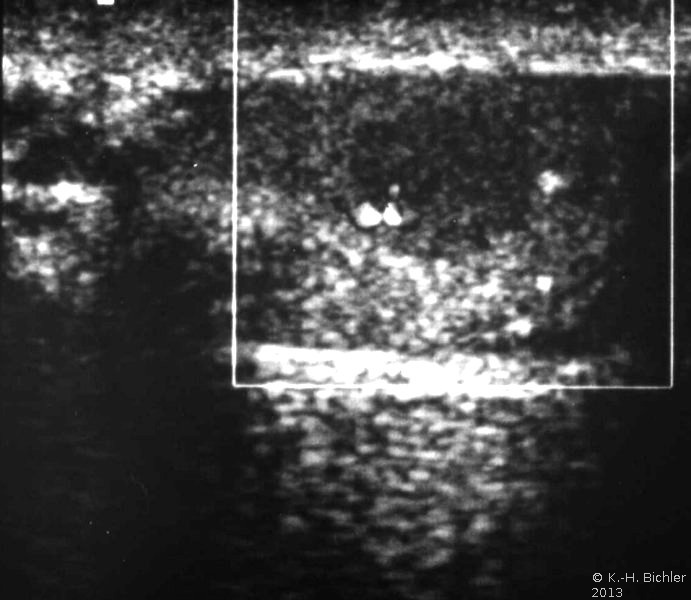

In der Sonographie finden sich abgekapselte Tumoren (Abbildung 6).

Anamnestisch bestand bei dem Jugendlichen bereits seit über einem Jahr eine beiderseitige Gynäkomastie. Die körperliche Untersuchung ergab einen derben Tumor am Oberpol des rechten Hodens. Beide Hoden insgesamt klein. Die Sonographie zeigte im rechten Hoden ein inhomogenes, umschriebenes tumorverdächtiges Areal (Abbildung 7a). Im Spermiogramm fand sich eine Oligozoospermie (< 1.000.000/ml). Die Tumormarker AFP und β-hCG im Normbereich. Die Werte von Testosteron, FSH, LH und Östradiol siehe Kurve. Auffällig war die Östradiolerhöhung (Abbildung 8).